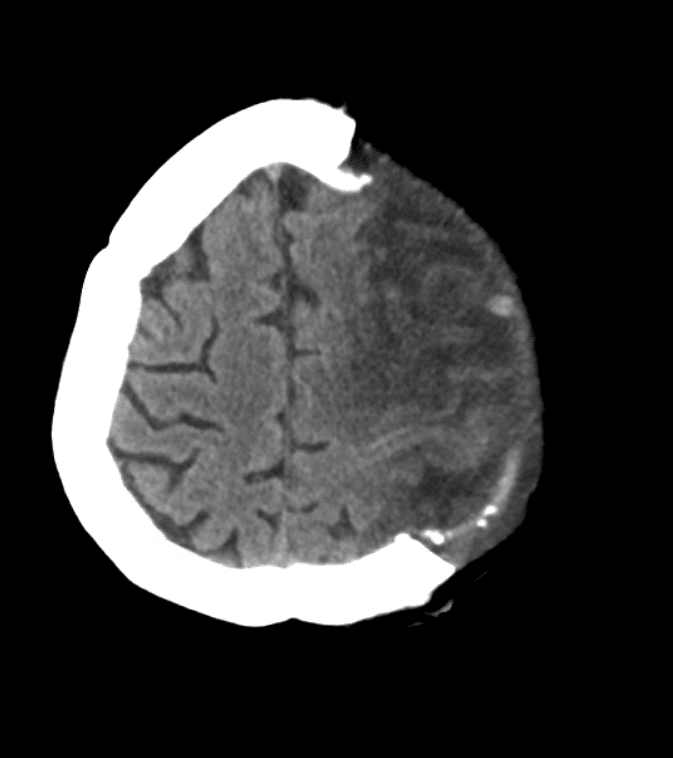

Immagini post operatorie